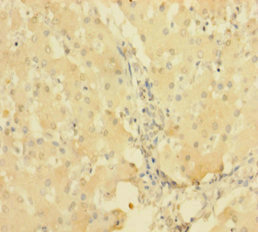

• Immunohistochemistry of paraffin-embedded human liver tissue using CSB-PA624019LA01HU at dilution of 1:100

• Immunohistochemistry of paraffin-embedded human kidney tissue using CSB-PA624019LA01HU at dilution of 1:100